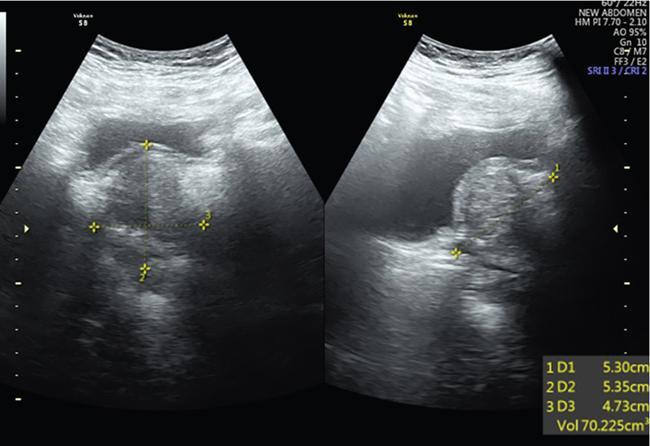

Suriyaprakash Nagarajan, Rupa Renganathan, Suhasini Balasubramaniam, Anupama Chandrasekharan, Kumarsampath Sumeena OVARIAN CYST VERSUS BLADDER Cystic lesions are common in female pelvis and mostly they originate from ovary. Ovarian cysts can arise from epithelial, stromal or germ cell components and can be benign or malignant cystic lesions. Pelvic Ultrasonography (USG) is the preferred imaging modality for evaluation of adnexal cystic lesions. Large simple ovarian cyst appears unilocular, anechoic with thin smooth walls. Such large simple cysts are confused with distended bladder. Distended bladder is a condition in which the urinary bladder is full and the patient is unable to void completely causing abdominal discomfort and pain. Distended bladder can be due to obstruction to passage of urine, neurological disorder or spastic sphincter. Differential diagnosis of cystic lesions in pelvis can be intraperitoneal, extraperitoneal and both intraperitoneal and extraperitoneal. Cystic lesions of intraperitoneal origin includes peritoneal inclusion cyst, paraovarian cyst, mucocele of appendix and hydrosalpinx. It is important to differentiate large simple ovarian cyst and distended bladder when patient presents with lower abdomen pain and the patient’s clinical history helps to make an accurate diagnosis (Table 11.4.1.1). UTERINE VERSUS EXTRAUTERINE MASS Ultrasound is usually the initial imaging modality for the pelvic mass. When USG findings are indeterminate to ascertain the organ of origin and to characterize, the next imaging modality is MRI due to its superior soft tissue resolution and multiplanar imaging capability (Figs. 11.4.2.1 and 11.4.2.2). Signs are demonstrated in Figs. 11.4.2.3 to 11.4.2.6. The sequences used in MRI pelvis are conventional T2WI in all three planes and T1WI in single plane. The problem-solving sequences are oblique coronal and oblique axial T2 along and perpendicular to the long axis of uterus in sagittal localizer. It can identify the organ of origin. Other sequences like T1 fat sat, diffusion-weighted imaging (DWI) and dynamic contrast T1WI with fat sat and subtracted images help to characterize the lesion further. BLADDER MASS VERSUS PROSTATE MASS Irregular mass lesions in the bladder neck are termed as ‘Bladder occupying lesions’. It is often difficult to determine whether the origin of these lesions is the bladder or the prostate gland. Transabdominal Ultrasound with colour Doppler studies and CT imaging do not usually delineate the origin of the lesions. The following features may aid in the differentiation (Table 11.4.3.1): History Painless haematuria Usually asymptomatic Investigations TAS, TRUS, MRI, Cystoscopy-guided biopsy PSA, DRE, TRUS, MRI, TRUS-guided biopsy At what point is the cross over between the two lesions T4 bladder cancer invading the prostate Aggressive prostate cancer protruding into the bladder Epicenter of the lesion Within the bladder Within the prostate gland Central necrosis in the mass Not commonly seen Seen in sarcomas IVU/CT urography Additional lesions in the urinary tract suggest that the bladder occupying mass in the bladder neck is of bladder-origin Prostate masses do not commonly cause masses in the urinary tract except for the very rare metastasis Virtual cystoscopy Additional lesions in the bladder wall and dome suggest that the bladder occupying mass in the bladder neck is of bladder-origin MRI T2 hypointensity Bladder masses are usually T2 hyperintense Seen in adenocarcinomas MRI T2 hyperintensity Bladder masses are usually T2 hyperintense Urothelial tumours infiltrating the prostate, neuroendocrine masses MRI T1 and T2 hyperintensity Bladder masses are usually T1 hypointense and T2 hyperintense Mucinous adenocarcinoma MRS Elevated choline values are seen in highly cellular masses Elevated choline:citrate ratio in prostate malignancies No significant finding in mucinous adenocarcinoma DWI Diffusion restriction is seen in malignant bladder masses No restriction in mucinous adenocarcinoma BPH versus bladder mass Exophytic BPH has signal intensities and appearance similar to and is contiguous with BPH within the gland OVARIAN MASS VERSUS PARAOVARIAN MASS Ultrasonography (USG) is the primary imaging modality in patients presenting with pelvic symptoms. Transvaginal, transabdominal or both should be performed in evaluation of such patients to differentiate ovarian and nonovarian origin of the lesions. Ovarian lesions can be a simple ovarian cyst, complex cyst with septations and solid components or a solid mass. Paraovarian lesions are remnants of the Wolffian duct in the mesosalpinx along fallopian tube or the ovaries and do not arise from the ovary. Paraovarian cysts are classified based on their site of origin into paratubal mesosalpingeal cysts, hydatid cysts of Morgagni, paraovarian cystadenoma and subserosal cysts. Differentiation of ovarian and paraovarian lesion poses significant diagnostic challenge. Both Computed tomography (CT) and Magnetic resonance imaging (MRI) are essential problem-solving tool in determining the site of origin of a pelvic mass. The first step in pelvic mass evaluation is to find out if it is ovarian or nonovarian in origin. Characterization of paraovarian or ovarian lesions is of utmost importance in order to optimize therapeutic procedures and it influences patients management (Figs. 11.4.4.1 and 11.4.4.2). Findings such as ovarian vascular pedicle sign, claw sign, bird beak sign and visualization of normal ovary helps to differentiate between ovarian and paraovarian lesions. Subsequently ovarian lesions should be categorized into benign, indeterminate and malignant masses (Table 11.4.4.1).